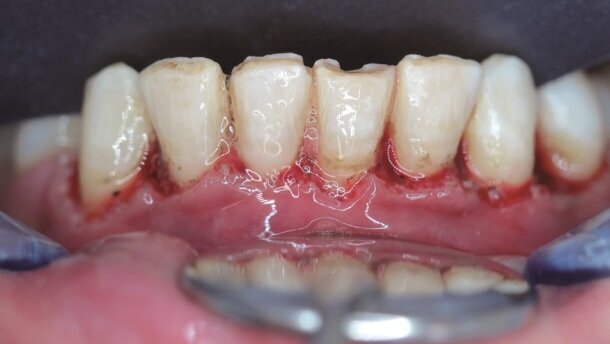

W związku z tym, przed przystąpieniem do zabiegu dokonano pomiarów głębokości szczelin dziąsłowych oraz – zgodnie z planowanymi wymiarami zęba – zanotowano szerokość, wysokość oraz ich stosunek (Tab. 1). Idealne proporcje wynoszą 0,8-0,9. Po ustaleniu proporcji, wodoodpornym markerem zaznaczono na powierzchni dziąseł granice cięcia (Ryc. 7). Ponieważ długość korony klinicznej była mniejsza od korony anatomicznej oszacowano, że należy usunąć ok. 2 mm dziąsła (Ryc. 8).

Tkanki dziąseł pacjentki charakteryzowały się grubym biotypem oraz odpowiednio grubym dziąsłem związanym. Rekonstrukcję dziąsła wykonano, używając następujących parametrów: średnia moc na wyjściu wynosiła 2,5 W, czas trwania impulsu to 700 µsec (tryb S), częstotliwość powtarzania impulsu wynosiła 50 Hz z zastosowaniem końcówki MZ5 przy minimalnym użyciu wody (powietrze: 10 – woda: 10). W pierwszej kolejności usunięto nadmiary dziąseł wg zaznaczonego wcześniej wzoru (Ryc. 9). Na koniec stworzono estetyczną symetrię dziąseł, a następnie przeznaczono 2 tygodnie na wygojenie do następnej fazy leczenia (Ryc. 10).

Pacjentka zgłosiła niewielkie krwawienie w dniu po zabiegu, jednak nie wystąpiły dolegliwości bólowe ani tkliwość. Gingiwektomię w żuchwie (Ryc. 11) wykonano na kolejnej wizycie wraz z wybielaniem zębów łuku górnego, po czym odczekano kolejne 2 tygodnie do wygojenia (Ryc. 12).